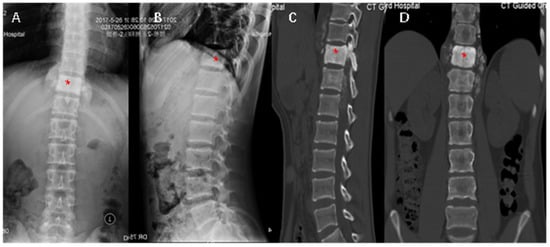

2. Case Report

2.2. Treatment